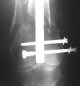

THX, initial images are

1,

2.

At that moment we had in stock only the 10 mm solid nails so of course there was no idea about early weight bearing. But it was quite enough for early knee ROM excersises (see attached). Two locking screws through the distal block provided that.